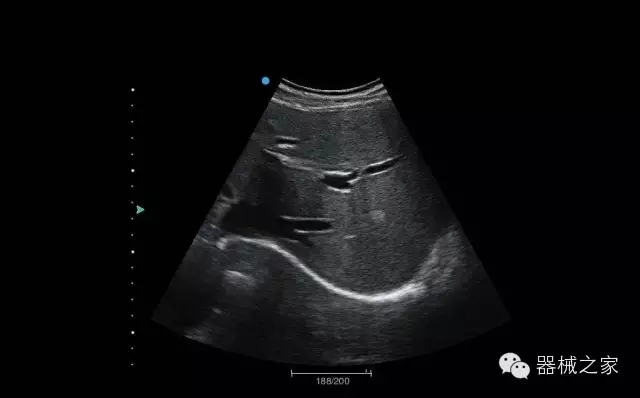

臨床圖片賞析

結(jié)甲

腎臟血流

肝血管瘤

產(chǎn)品特點(diǎn)

·屏幕可左右90度旋轉(zhuǎn);

·雙模操控;

·兩用提手;

·雙鋰電池;

·超輕機(jī)身;

·15寸高亮高清醫(yī)學(xué)顯示器;

·衛(wèi)星布局操控面板;

·一體化剪切板;

·多功能導(dǎo)航鍵;

“宏云”平臺

·采用移植自高端臺式彩超的“宏云”平臺技術(shù),使系統(tǒng)具有更優(yōu)秀的圖像效果;

人性化的設(shè)計(jì)

·內(nèi)置電池,輕巧的外觀設(shè)計(jì)以及臨床功能、軟硬件設(shè)計(jì)的人性化設(shè)計(jì),使系統(tǒng)在臨床多科室移動(dòng)診查中,均從容應(yīng)對;

Fusion THI二代融合諧波成像

·在不同諧波頻率段獲得的信息進(jìn)行實(shí)時(shí)融合,既能獲得諧波圖像分辨率又能提高圖像的穿透力,降低圖像噪音;

XBeam多域復(fù)合成像

·通過頻域和空域角度進(jìn)行復(fù)合的圖像處理,能有效消除由于圖像離散化和圖像衰減引起的空間分辨率下降的不利影響,彌補(bǔ)原有圖像空間分辨率的不足,獲得更加清晰的圖像;